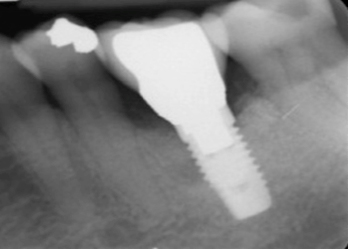

Fig 17. Radiograph showed symmetrical infrabony defect affecting 50% of the implant surface.

Figure 17